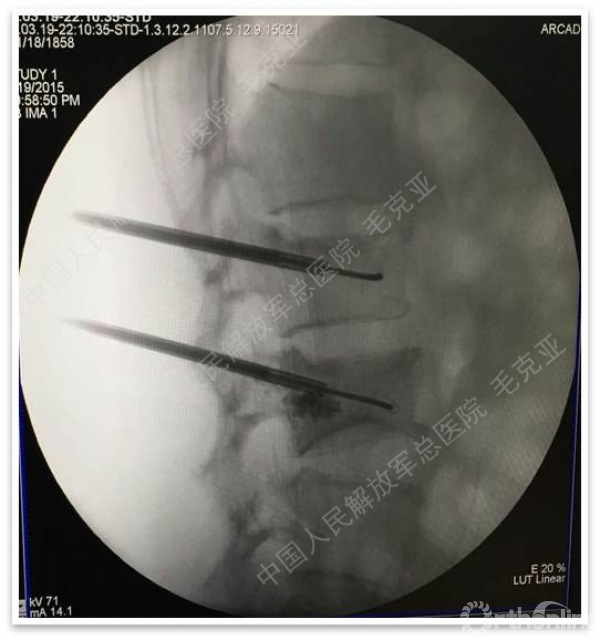

导语:随着社会老龄化的不断加速,骨质疏松性椎体压缩骨折作为一种普遍存在的老年骨科疾病已经成为现今骨科界的一个热点话题。传统的保守疗法治疗效果不佳,而现有的椎体增强技术又具有多种风险和缺陷。针对这种现状,中国人民解放军总医院毛克亚教授提供了一种新的解决方法。